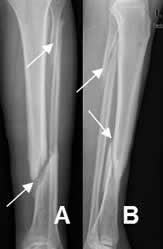

Fig 34. Fractura transversa.

A: Rx AP y B: TAC reconstrucción coronal. Fracturas transversas en el húmero distal y el maléolo externo.